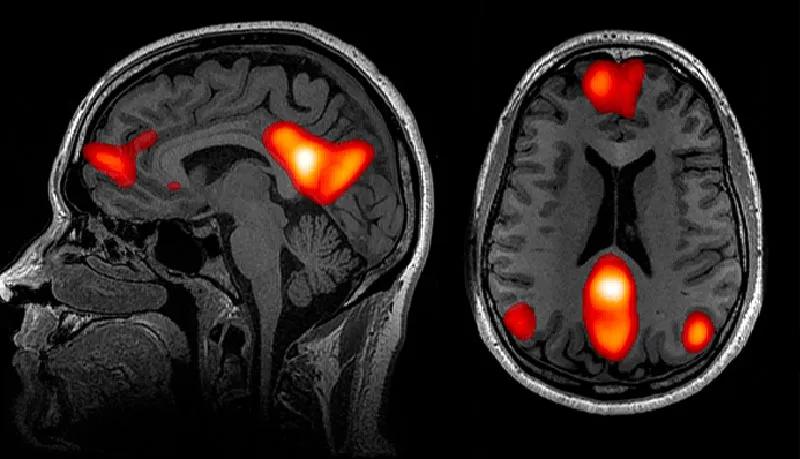

该研究2020年刊登于《自然-通讯》[21],其结果揭示了孤独感与当我们精神上处于待命状态时保持活跃的大脑默认网络(default network)密切相关。尽管研究表明默认网络中的活动消耗了大脑的大部分能量,“直到20年前我们都还不知道这一网络系统的存在。”比兹多克说。

比兹多克和他的团队发现长期孤独者的默认网络中某些区域的灰质体积不仅更大,而且他们的默认网络与大脑其他区域的连接也更紧密。此外,默认网络似乎参与了人类演化出的例如语言、预测未来和因果推理等独特能力的运用。更笼统地说,当我们想到他人时[22],包括当我们分析他们的意图时就会激活默认网络。

人脑的功能磁共振成像揭示了与默认网络相关的一些区域——当我们想到他人时最活跃的神经中枢区域。—

John Graner,Terrence Oakes,Louis French and Gerard Riedy

心理学家早就发现,孤独的人往往会做社会互动的白日梦,容易怀念过去的社交事件,甚至拟人化他们的宠物[23],例如,与猫交谈。有关默认网络连接的研究,为该心理学发现提供了神经成像方面的证据,比兹多克说:“想要在心理上完成幻想需要默认网络做出相应的配合。”